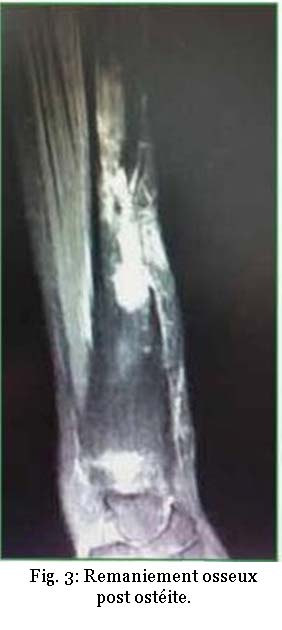

Après ce temps, l’examen clinique palpatoire ostéopathique débute, l’ostéopathe va apprécier la mobilité des articulations, le tonus musculaire, l’ampliation respiratoire, la sphère abdominale, mais aussi la vascularisation des téguments, la qualité de la peau (fig. 3 et 4).

La chaleur ou la froideur d’une zone, la finesse ou la transparence des téguments ou une sudation locale, et les adhérences cicatricielles sont autant d’éléments diagnostiques.